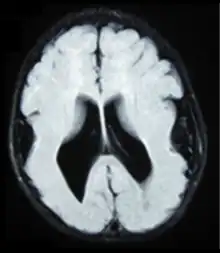

Brain MRI, T1 weighted on a transversal plane, of an 8-month old boy with lissencephaly. Note the scarce and wide gyri, mostly on the parietal, temporal and occipital lobes, the absence of a true Sylvian fissure, and the augmented thickness of the gray matter. The boy had a severe developmental delay and seizures.